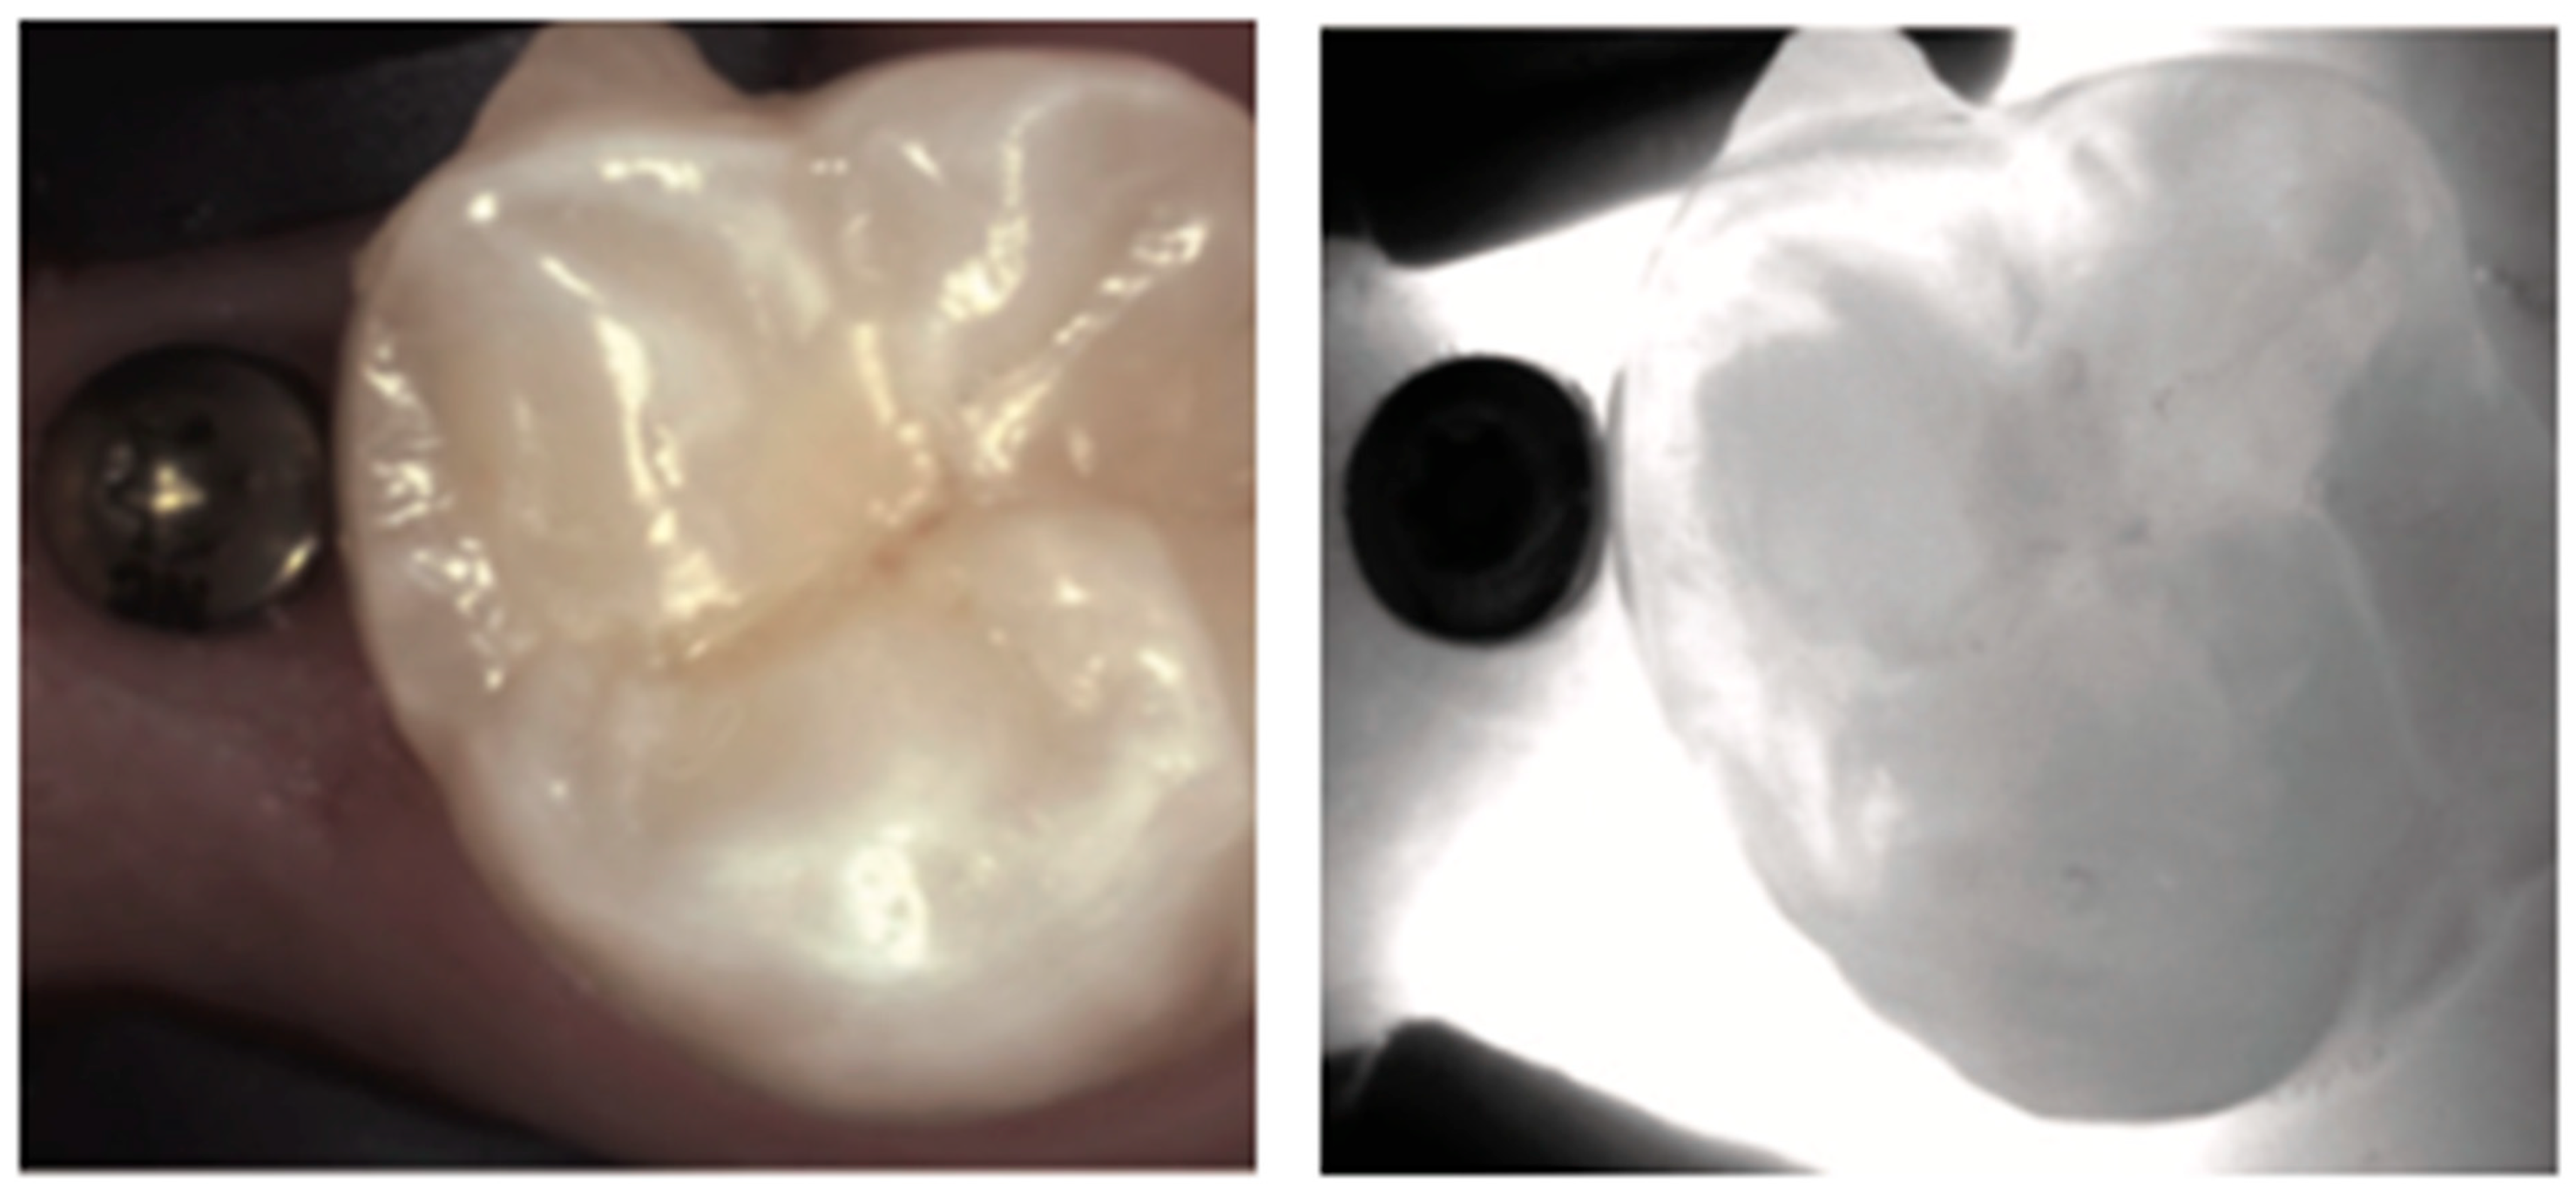

3. Restored Teeth